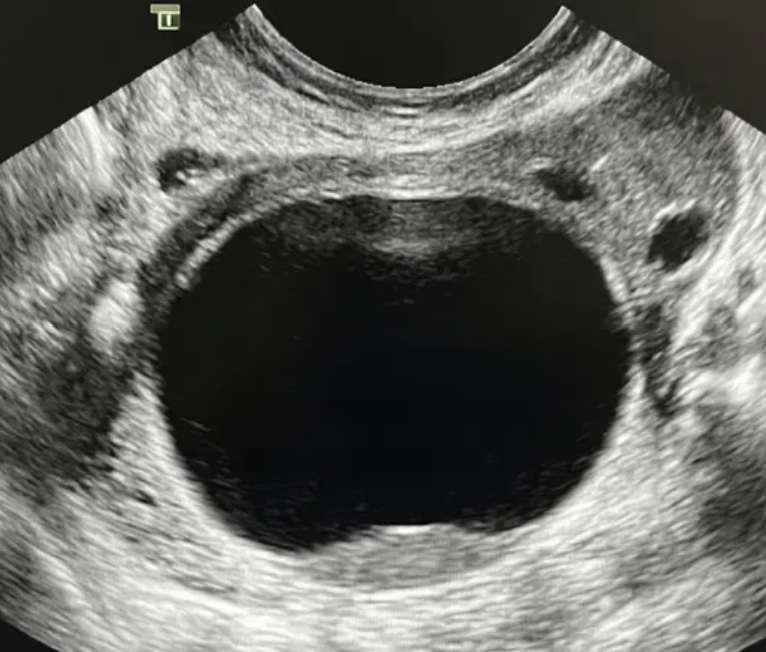

Risco: <10%Cisto unilocular ≥ 10 cm, cistos dermoides/endometriomas/hemorrágicos ≥ 10 cm, cisto unilocular com parede irregular < 3 mm, cisto multilocular < 10 cm com parede lisa, lesão sólida com superfície lisa.

Achados ultrassonográficos

Conduta

Se não removida cirurgicamente, considerar seguimento com US em 6 meses. Se sólido considerar US com especialista (se disponível) ou RM (com classificação O-RADS MRI). Seguimento com ginecologista.